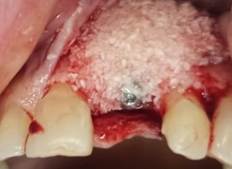

A 24-year-old male patient who required extraction of the upper left central incisor due to a corono-radicular fracture, reason for which is requested, panoramic radiography and cone beam, in which, as in the immediately previous case, the extraction was planned using a two-armed lever as an atraumatic alveolar preservation technique. During the clinical examination, it was observed at the level of the upper left central incisor, resin filling of 4 surfaces and slight redness was evident at the gingival margin (Figure 3.A and Figure 3.B). The extraction procedure was initiated by applying the strength of the two-arm lever, the straight elevator is in a horizontal position resting on the mesial and distal surfaces have the greatest possible palatal rest and resistance in the mesial and/or disto-vestibular areas; that generates an extrusive dental dislocation that combined with the vestibular palatine grip with the left hand helps to avoid compromising the vestibular table, then it is produced in the first instance, tooth crown extraction (Figure 4.A and Figure 4.B), by the corono-radicular fracture already mentioned, then its proceed to the dental root´s extraction, using lever of the second degree, without compromising the vestibular and palatal tables. Once confirmed the integrity of the vestibular wall and the gingival biotype: type I socket, 1cc of Puros® particulate cortical bone (250-1000 microns) is used for the graft. Subsequently, Zimmer TSV 3.7 * 13mm implant was placed (Figure 5). The implant was prepared and placed 2.5mm from the gingival margin to achieve primary fixation, a surgical cover screw was placed, the cavity was occluded with a collagen membrane (CollaTape®) and sutured transverse and horizontally with acid polyglycolic 5-0, followed by a provisional restoraion, finally, the patient is prescribed oral capsules of dicloxacillin 500mg and nimesulide tablets orally 100mg. After five months of clinical and radiographic controls, the second phase begins. The patient received a metallic ceramic crown with functional and aesthetic results after 18 months of continuous controls.

A 36-year-old male patient who required extraction of the upper left central incisor due to radicular-crown fracture as the anterior case, finding a type II socket with a dehiscence of 25% by this reason it is decided follow the protocol to the extraction procedure initiated by applying the strength of the two-arm lever, then 1cc of puros particulate cortical bone (250-1000 microns) is used for the graft. Subsequently implant was placed (Figure 6.A and Figure 6.B).